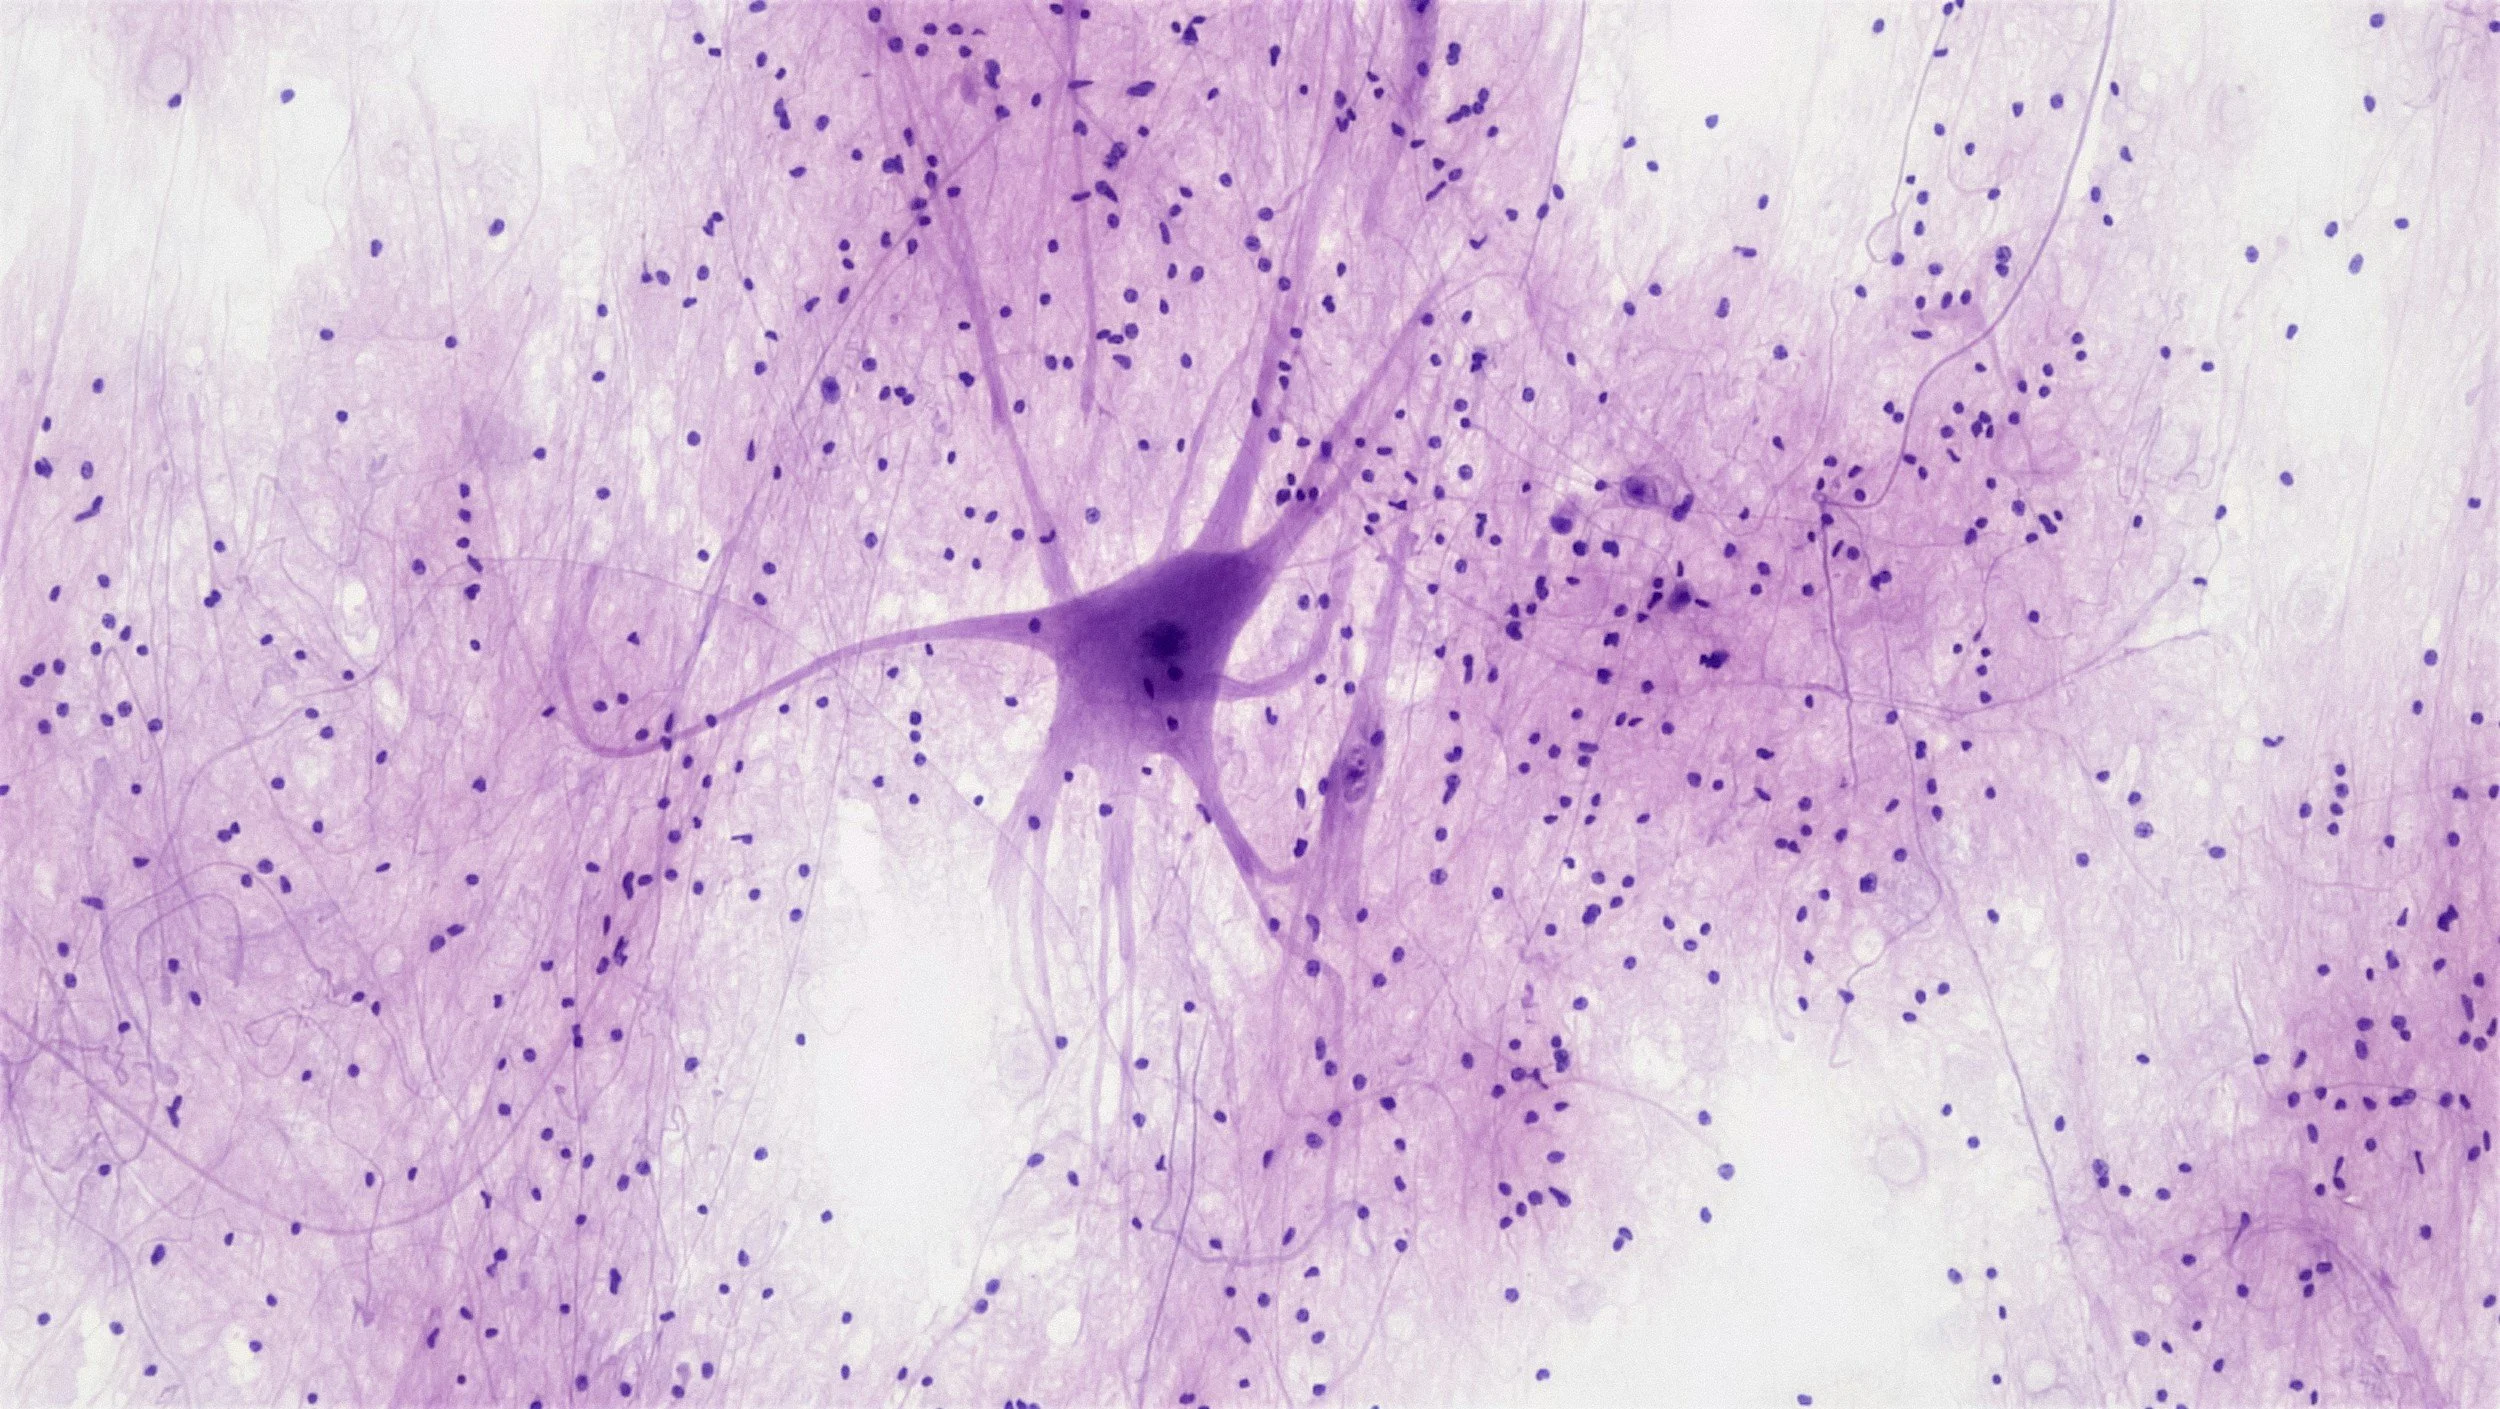

The Dawson Lab investigates neuronal cell death and survival in Parkinson’s disease (PD), stroke, and related disorders.

We discovered Parthanatos, a regulated cell death pathway critical in ischemic injury and PD. This mechanism involves PARP activation, mitochondrial release of apoptosis-inducing factor (AIF), and recruitment of MIF nuclease, which executes DNA cleavage. Our team identified the first MIF nuclease inhibitor, showing robust neuroprotection in multiple PD models.

The lab has also made pioneering contributions to PD biology. We revealed that parkin is a ubiquitin E3 ligase inactivated by mutations, nitrosylation, or c-Abl phosphorylation, and we identified its key substrates (PARIS/ZNF746, AIMP2, NLRP3). These discoveries drove the development of parkin activators and c-Abl inhibitors, now in clinical trials. We further showed that DJ-1 is a peroxidase protecting mitochondria, and that LRRK2 mutations enhance kinase activity linked to neurodegeneration, leading to the first protective LRRK2 kinase inhibitors. We also identified LAG3 as the receptor for α-synuclein transmission and helped develop NLY01, a GLP-1 receptor agonist currently in clinical testing.